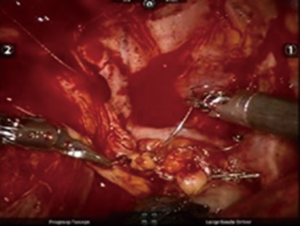

After inserting the ports, the robot was docked. We performed the approach using the three-arm video-assisted thoracic surgery (VATS)-based technique described elsewhere (14). The anterior arm was inserted through a utility incision (Figure 1). The four-arm VATS-based approach was used only in one patient who underwent isolated bronchial resection. The use of V-loc sutures was preferred in the last six cases (Figure 2). As a rule, a prostate bulldog clamp was used to stabilize the first suture (Figure 3). We routinely covered the anastomosis or suture line with pleura, pericardial fatty tissue or rarely with thymus (Figure 4).

Some surgeons prefer three- or four-arm robot-assisted thoracoscopy with a utility incision, whereas others prefer complete portal robotic surgery (15,22). Insufflation with CO2 provides pneumothorax and sufficient exposure in the latter technique (23). We prefer the three-arm robot-assisted videothoracoscopically-based surgical technique, and the differences between the two techniques are described in a study of one of us (14). We use a bulldog prostate clamp to stabilize the first suture of a sleeve anastomosis, which makes the procedure easier and allows the operation time to be shorter.